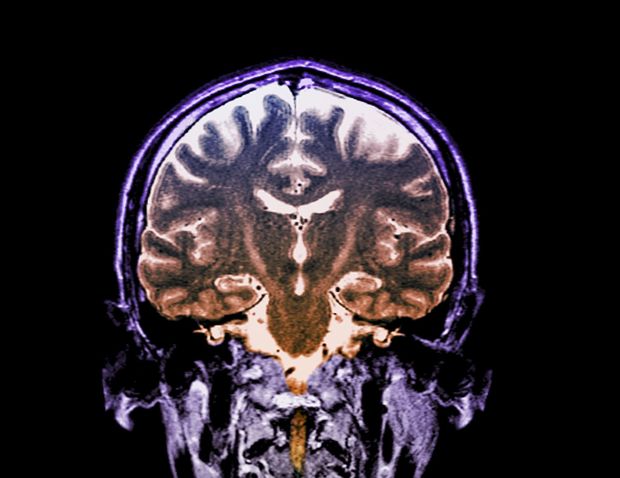

Quelque 200 nouveaux patients sont diagnostiqués chaque année en Belgique. A l'échelle du globe, ils sont 120.000. La SLA ou sclérose latérale amyothrophique est incurable et mortelle à terme et continuera de l'être pendant longtemps encore faute d'investissements dans la recherche. L'origine de la maladie, qui paralyse les groupes musculaires un par par un entraînant la mort du patient dans les trois à cinq ans après le diagnostic, est donc toujours un mystère et le moyen de la guérir inconnu.